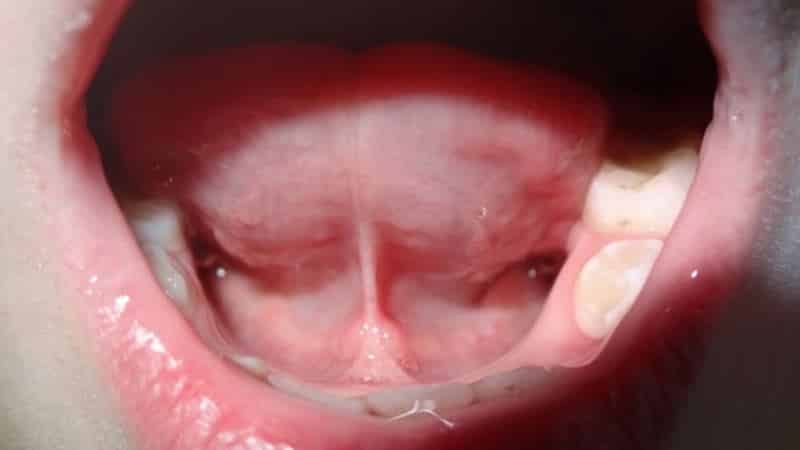

У детей может наблюдаться как полная, так и частичная короткая уздечка языка. В первом случае это приводит к ограничению подвижности языка, и при осмотре можно заметить, как язычок сворачивается в трубочку с обеих сторон. При частичной короткой уздечке присутствует тонкая пленочка, в которой отсутствуют нервные окончания. Родители могут ознакомиться с изображениями полной короткой уздечки у новорожденных, чтобы определить наличие признаков у своего малыша.

Сравнивая фотографии короткой уздечки языка у новорожденных, родители могут лучше понять аномалию и сопоставить с состоянием ротовой полости своего ребенка.

Можно ознакомиться с фотографиями, на которых видно, как выглядит короткая уздечка языка у ребенка до и после операции. После вмешательства у малыша постепенно исчезают анатомические дефекты, улучшается дыхание, а также наблюдается значительное увеличение веса. Повышается вероятность предотвращения неправильного прикуса и устранения проблем с речью.